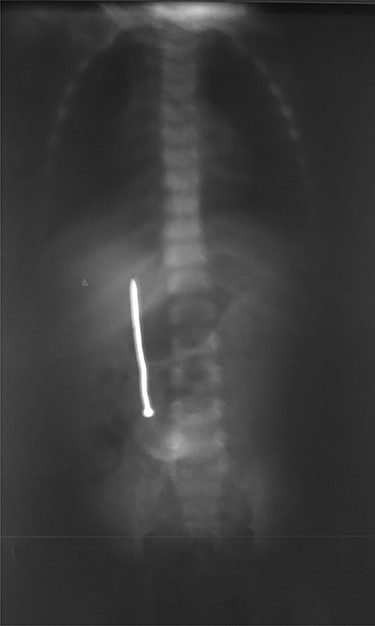

Abdominal examination was normal. A repeat abdominal radiography was done. The nail’s position had not changed from the first X-ray site, with no free peritoneal air (Fig. 2).

In our case, according to the nail’s position on abdominal radiography, perforations were probably due to duodenal wall extension and progressive erosion of the nail’s head through the duodenal wall [3–5]. Our patient did not present signs of peritonitis neither free peritoneal air (pneumoperitoneum) because the site of duodenal perforation was covered by adjacent loops of ascending colon. This avoids the passage of intraluminal air into the peritoneal cavity.

Plain radiography plays the main role both in the diagnosis and the choice of operative interventional moment—either by pinpointing the radio-opaque image, or by showing certain FB characteristics, or by noting images suggesting complications (absent in our case), or even by projecting the FB in the same place over a period of time, an aspect inductive of fistula. In our case, right-edge superposition of the FB image upon the lumbar spine is characteristic of FB positioning in the second part of duodenum [5, 6]. Its persistence in the same place (the second part of the duodenum as in our case) suggests the presence of a duodenal fistula or perforation, which requires surgical intervention [7].